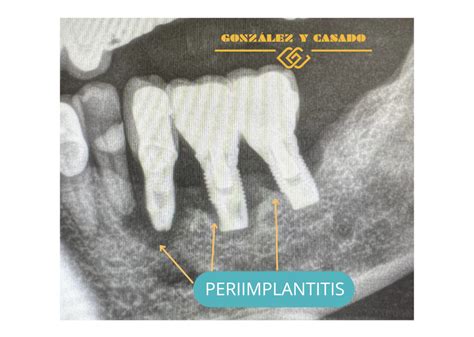

- Periimplantitis: Si no controlamos la mucositis, se puede producir la falta o pérdida de tejido óseo y, a largo plazo, la pérdida del implante.

La periimplantitis es una enfermedad periimplantaria crónica de origen inflamatorio que afecta los tejidos (encía y hueso) que rodean un implante dental. En esta condición, la encía alrededor del implante se inflama y, en casos avanzados, se produce una pérdida progresiva del hueso de soporte del implante. Es importante diferenciarla de la mucositis periimplantaria. La mucositis periimplantaria es la etapa inicial, donde existe inflamación de los tejidos blandos (encía) alrededor del implante sin pérdida ósea; es una afección reversible si se trata a tiempo. La periimplantitis, en cambio, es un estadio más grave en el que la inflamación ha progresado y ya hay destrucción del hueso que sostiene al implante.

Periimplantitis: Inflamación y pérdida ósea alrededor de un implante dental.

- Radiografías dentales: La confirmación de la periimplantitis suele requerir radiografías, típicamente radiografías periapicales o panorámicas de la zona del implante. En la radiografía buscamos evidencias de pérdida ósea alrededor del implante comparado con radiografías tomadas justo después de colocarlo. Un signo típico es un cráter o sombra alrededor de la rosca del implante indicando que el hueso se ha reabsorbido. Si disponemos de radiografías anteriores, podemos determinar cuánto hueso se ha perdido con el tiempo. Incluso una pérdida ósea mínima (por ejemplo 2-3 mm) acompañada de inflamación nos haría diagnosticar periimplantitis incipiente.